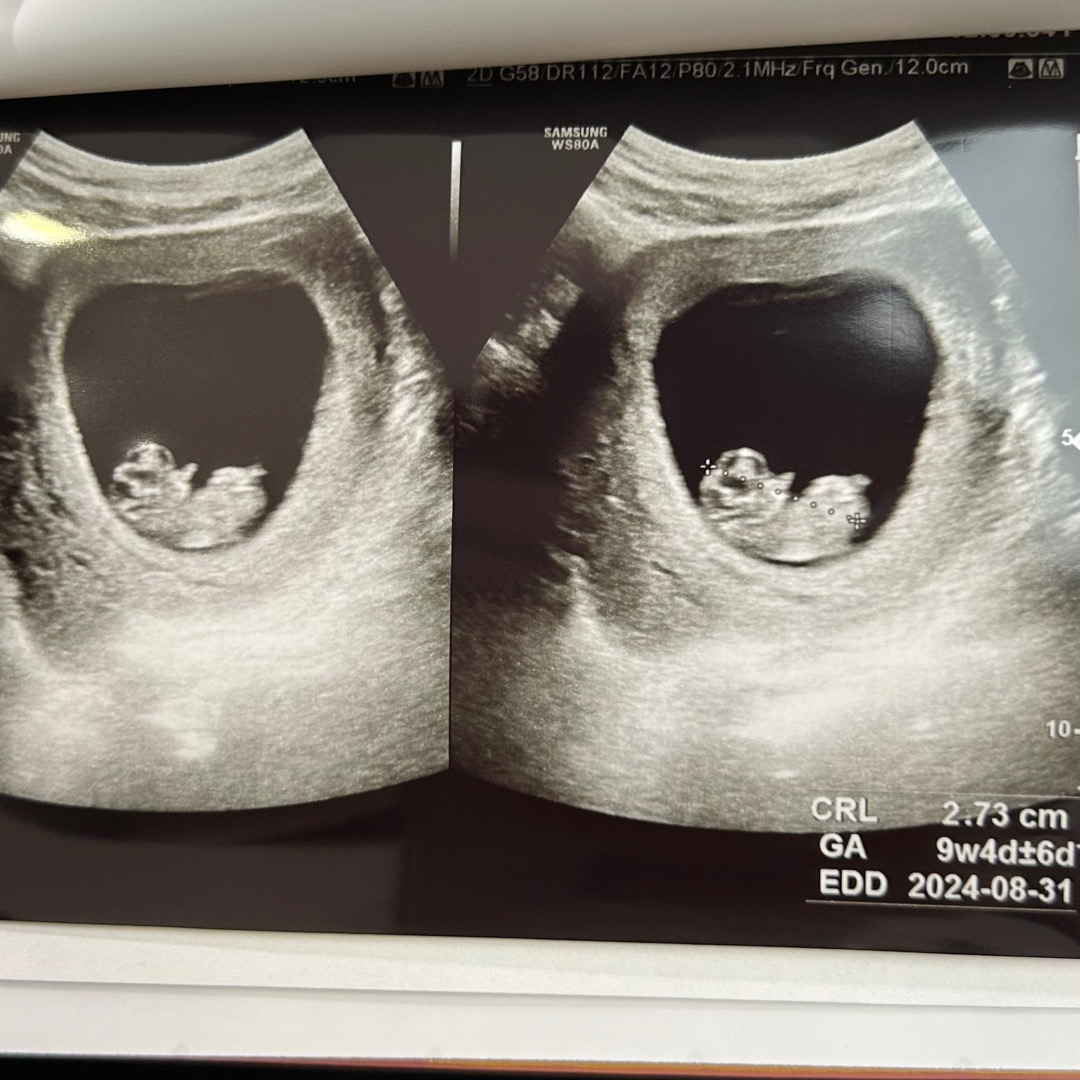

9주 4일차 초음파 보구 왔어용🤍

꾹 참고 2주 기다렸다가 간 오늘! 9주 3일인줄 알았는데 또 하루 줄었네요 ㅎㅎ 아기는 주수에 맞게 아주 건강히 잘 있다하여 다행입니닷 ㅎㅎ 심소도 182 bpm 저번보다도 빨라졌네용 기대하던 젤리곰 조금씩 움직이는것두 보고 신기했어요👼🏻🤍 이제 3주뒤에 기형아검사인데 어떻게 기다리죠ㅠ